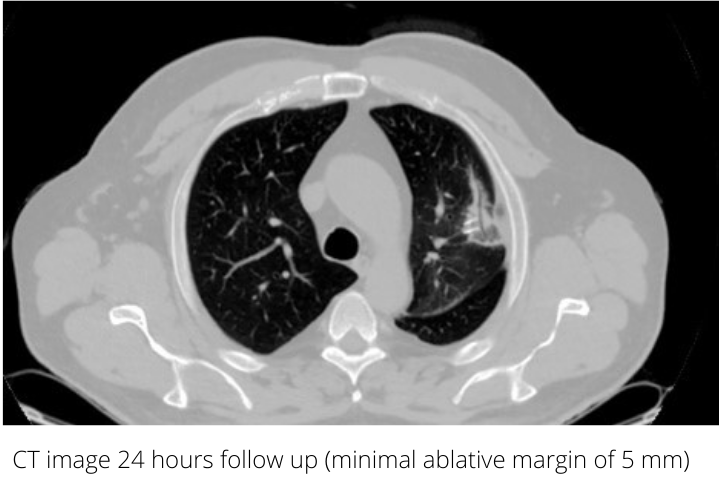

Control CT scan was acquired on the next day, the ablation zone was visible clearly around the tumor with the minimal ablative margin of 5 mm. As the biology of the primary cancer was not very aggressive, the patient was followed-up every 6 months for two years. Ablation zone consolidation and shrinkage were observed over the time without any signs of local tumor progression. Ablation should always be considered when treating oligometastatic disease.